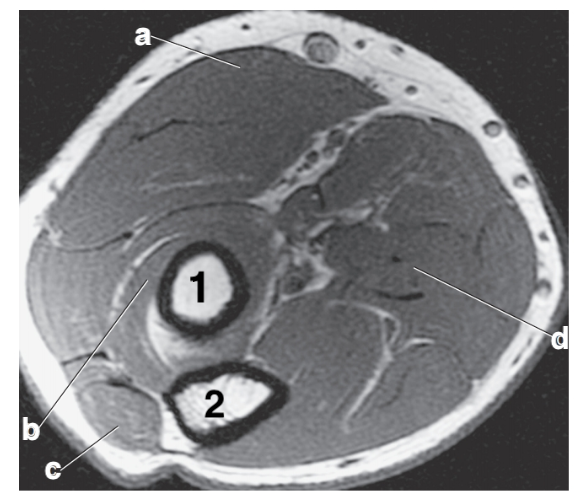

Number 2 is on the __________ side of the patient.

lateral

What anatomy is # 3?

fibula